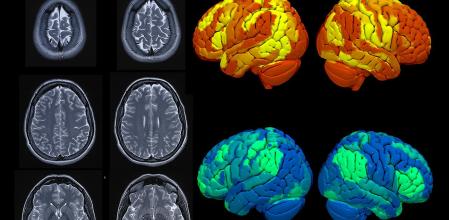

En neurología moderna, son absolutamente fundamentales las técnicas diagnósticas, ya que el cerebro y el sistema nervioso son estructuras extraordinariamente complejas que no pueden explorarse directamente, sino a través de herramientas especializadas para “ver” qué está ocurriendo en su interior. Sanitas CIMA dispone de un arsenal diagnóstico completo que incluye técnicas de imagen avanzada como la resonancia magnética de 1.5 teslas y la tomografía computarizada, que permiten visualizar la estructura cerebral con gran detalle. No son las únicas.

“La medicina nuclear con PET y SPECT añade información funcional y metabólica crucial en enfermedades neurodegenerativas y oncológicas. La neurosonología, mediante Doppler carotídeo y transcraneal, nos permite evaluar el flujo sanguíneo cerebral de forma no invasiva, fundamental en la prevención y seguimiento de enfermedades vasculares cerebrales. Por su parte, la neurofisiología clínica –con electroencefalograma, electromiografía y estudios del sueño– registra la actividad eléctrica del cerebro y los nervios, revelando alteraciones funcionales invisibles a otras técnicas”, detallan desde Sanitas CIMA.

El diagnóstico se completa con herramientas de vanguardia como los test neuropsicológicos para evaluar funciones cognitivas, el análisis de biomarcadores en líquido cefalorraquídeo y estudios genéticos que identifican mutaciones causantes de enfermedades hereditarias. Una combinación inteligente de técnicas que permite al hospital, no solo confirmar diagnósticos, sino también personalizar tratamientos y monitorizar su eficacia, mejorando significativamente el pronóstico de sus pacientes.